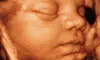

Experimenta la última tecnología en ecografías emocionales 4D y 5D con una matrona, y crea recuerdos inolvidables viendo a tu bebé

¿Te gustaría tener una conexión más cercana con tu bebé antes de su llegada? De la mano de una matrona, verás a tu bebé, escucharás su latido y te informarán sobre la posición, el cordón umbilical y muchas cosas más. Con una ecografía emocional, podrás ver cada detalle del desarrollo de tu pequeño. Disfruta de imágenes avanzadas mientras compartes un momento especial y escuchas los latidos de su corazón.

Centro Mi Maternidad ofrece una experiencia integral para las familias durante su viaje de maternidad. Con un enfoque integral, el centro ofrece apoyo desde la preparación del embarazo hasta el posparto. Las ecografías avanzadas con tecnología 4D y 5D permiten a los futuros padres establecer una conexión emocional única antes del nacimiento. Además, ofrecen talleres especializados para familias que abarcan desde primeros auxilios hasta masaje infantil.